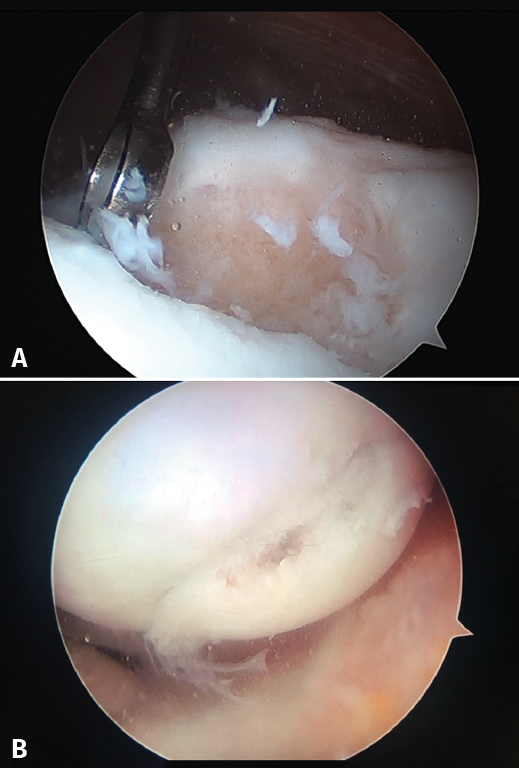

Although cartilage damage is most often of idiopathic or degenerative origin, joint cartilage injuries are also frequently caused by traumatisms (Figure 1A), i.e., joint trauma, followed by osteochondritis dissecans (OCD)(1,2) (Figure 1B).

The chondral defects may be partial or complete, depending on whether the full thickness of the cartilage is affected, with involvement of the subchondral bone. In this case a repair mechanism is activated that does not produce normal cartilage but rather repair tissue lacking the biomechanical characteristics of healthy hyaline cartilage, due to a decrease in type II collagen, which is replaced by type I collagen. In addition, the chondrocytes are replaced by fibroblasts, which are unable to produce an extracellular matrix with the adequate concentration of type II collagen(3,4) (Figure 2).